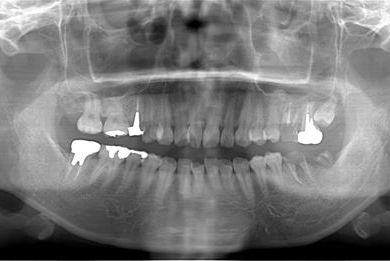

インプラントの症例写真 IMPLANT

骨再生スピードインプラント治療+歯肉歯槽骨整形手術

| 治療方針 | 左上下奥の保存不能の歯を抜歯し、インプラント治療にて機能的・審美的回復を行う。左上部分はソケットリフトにて上顎洞を拳上し、インプラント治療を可能にする。 | ||||||||||||||||||||||||||||||||

| 治療内容 | インプラント3本(抜歯即日スピードインプラント、ソケットリフト)、メタルボンドセラミッククラウン4本(メタルボンド用土台1本)、ハイブリッドセラミッククラウン1本 | ||||||||||||||||||||||||||||||||